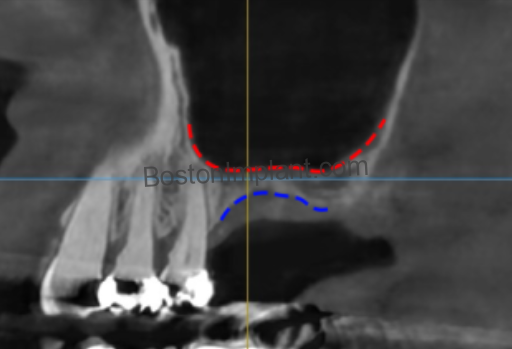

- Prevention & Clinical Protocol: Recent research shows a strong correlation between gum tissue thickness and membrane thickness. Dr. Lee utilizes high-resolution 3D CBCT imaging to map your specific anatomy before surgery. This allows for a customized approach that respects these delicate boundaries.

The lateral wall of the sinus contains small blood vessels that must be navigated carefully during the creation of the surgical window.

- The Risk: Approximately 10% of patients have larger vessels in this area that could cause significant bleeding if not identified during planning.

- Prevention & Clinical Protocol: Through “Vessel Mapping” via 3D CBCT imaging, Dr. Lee identifies the exact location of these vessels and plans the surgical access to bypass them entirely.